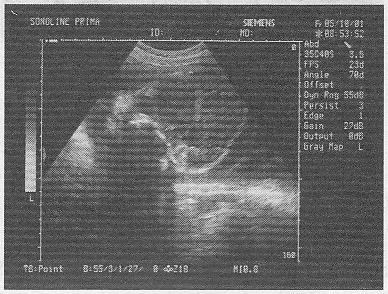

2.女,29歲,停經(jīng)28周,產(chǎn)前超聲檢查如圖,最可能的診斷為

正確答案:D 解題思路:顱骨強(qiáng)回聲光環(huán)消失,眼球突出呈蛙樣面容且羊水過(guò)多。